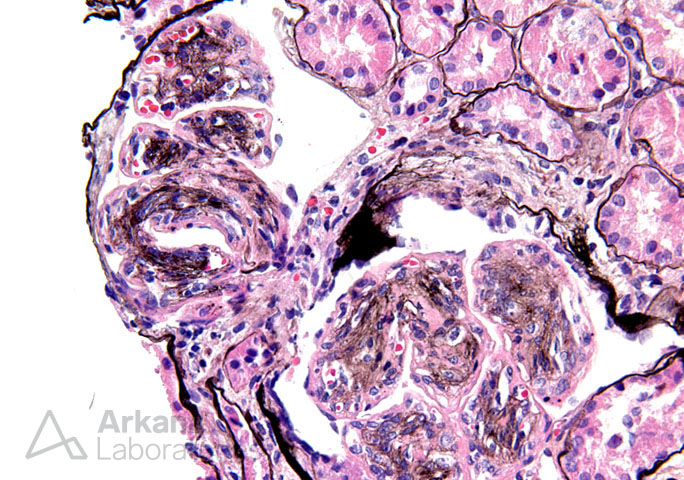

Previous Image Next Image Mesangioendocapillary Proliferation with Lobular Accentuation_4 Like Loading...